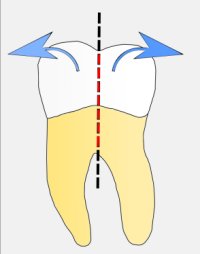

Na czym polega premolaryzacja?

Jest to przecięcie wzdłuż zęba trzonowego, z reguły dolnego, na dwie części

tak aby powstały dwa przedtrzonowce (zdjecie poniżej)